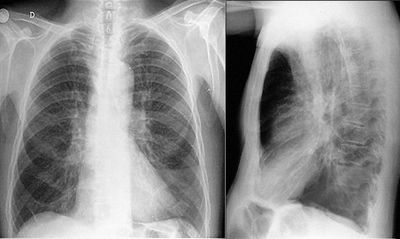

Identificação: LF, 67 anos, masculino, casado, pintor de carros aposentado, procedente de Sobradinho-DF. Queixa Principal: Tosse, falta de ar e febre há 2 dias. HDA: Tosse com expectoração esbranquiçada há dois anos, com piora progressiva. O quadro acompanhava-se de falta de ar aos esforços e chiado no peito esporádico. Em seguimento ambulatorial com diagnóstico espirométrico de DPOC, fazia uso irregular da medicação e não cessou o tabagismo. Há seis meses refere piora da tosse, que se tornou mais persistente e com pouca expectoração mucosa. Relata piora da tosse, com expectoração amarelada e febre não aferida há 2 dias. Antecedentes pessoais: Refere HAS, dislipidemia e cardiopatia. Nega DM e passado de TB; Antecedentes familiares: Pai falecido por IAM aos 50 anos, mãe e irmãos vivos e hígidos; Medicações em uso: anlodipino 10 mg/dia, AAS 100 mg/dia e sinvastatina 20 mg/dia. Hábitos de vida: Tabagista de 50 anos/maço; ex-etilista de fermentados aos finais de semana. Exame físico:Bom estado geral, desperto, orientado, corado, dispneico, acianótico, anictérico, febril. FC=82 bpm, PA=120x70 mmHg, Tax=38,6 ºC, FR=26 irpm, SatO2 86% em ar ambiente. Ritmo cardíaco regular em dois tempos, bulhas hipofonéticas Tórax com aumento do diâmetro antero-posterior, murmúrio vesicular diminuído e presença de raros sibilos. Crepitações grossas difusas, crepitações finas em base esquerda. Abdome normotenso, indolor, sem visceromegalias palpáveis, ruídos hidroaéreos presentes. Extremidades com pulsos periféricos presentes e simétricos, sem edemas. Gasometria arterial: pH 7,30 PaO2 56 mmHg SatO2 85% em ar ambiente PaCO2 52 mmHg HCO3 26mEq/L AG: 20 BE -4. Laboratório: Hematócrito: 47,5% Hemoglobina: 15,6g/dL Leucometria: 15700 (10% bastões) Plaquetas: 280.000 Creatinina: 1,5 mg/dL Potássio: 4,2 mEq/L Sódio: 138 mEq/L Glicemia: 94 mg/dL Conduta inicial: Iniciado O2 suplementar pormáscara de Venturi 30%, 15L/min. Nebulização com 10 gotas de berotec e 20 de atrovent. Hidrocortisona 200 mg, endovenosa. Colhidas hemoculturas e escarro para gram e cultura. Persistiu com sintomas inalterados após as medidas iniciais. A baciloscopia de escarro e o PCR para BK foram negativos. A melhor opção antibiótica inicial, dentre as abaixo é:

Ainda sobre o caso acima, a melhor estratégia ventilatória na sequencia do atendimento seria:

Answer

• Ventilação Pulmonar Invasiva

• Máscara não reinalante

• Ventilação pulmonar não invasiva, CEPAP

• Ventilação pulmonar não invasiva, BIPAP

Question 13

Question

Ainda sobre o caso acima, a melhor interpretação para a gasometria seria:

• Acidose respiratória crônica agudizada com hipoxemia

• Acidose mista com com hipoxemia

• Acidose respiratória aguda com hipoxemia

• Acidose metabólica de âniom gap elevado com hipoxemia